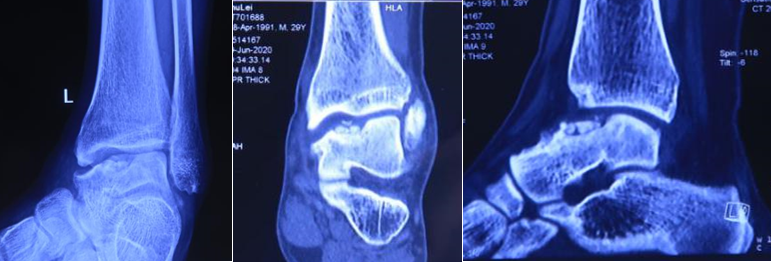

患者 , 男 , 28岁 , 左踝关节疼痛1年 , 加重3个月 , 影像学表现为左距骨内髁坏死、塌陷 , 面积约3*2cm大小 。 距骨坏死的治疗 , 对直径在2cm以内的距骨坏死 , 可以采用自体股骨髁骨软骨移植、自体带骨膜髂骨移植等方法 , 但对于直径超过2cm的距骨坏死 , 尤其是年轻患者 , 一直是治疗的难点 。 搜索国内外文献 , 对于超过2cm距骨坏死 , 一般采用踝关节融合、踝关节置换、同种异体距骨移植、全距骨置换等方法 。 但上述方法均有弊端:采用关节融合 , 患者丧失踝关节功能;踝关节置换、全距骨置换对于年轻、距骨单髁坏死患者 , 创伤大 , 且需要多次的返修手术;国外有采用同种异体新鲜距骨移植的报道 , 但目前国内还没有相关的骨组织工程库 。 经手术团队术前充分讨论 , 认为3D打印技术因其个性化的设计已经越来越多地应用于临床 , 决定对患者行3D打印距骨部分置换手术 。

术前患者的影像情况